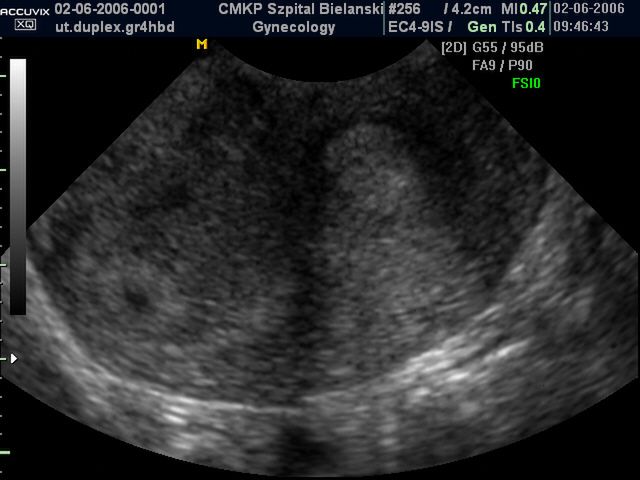

Płód w 4 tygodniu ciąży

W 4 tygodniu widać główkę dziecka, na której wyróżnić można jamę ustną, dodatkowo zaczyna pracować serce. Bije od 21 dnia ciąży.

/ 1Płód w 4 tygodniu ciąży - wielkość płodu

Pod koniec 4 tygodnia dziecko jest wielkości porównywalnej do ziarenka ryżu.